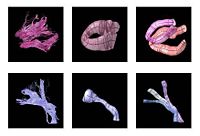

Fiber Tract Modeling, Clustering, and Quantitative AnalysisThe goal of this work is to model the shape of the fiber bundles and use this model description in clustering and statistical analysis of fiber tracts. More... |

Joint Registration and Segmentation of DWI Fiber TractographyThe goal of this work is to jointly register and cluster DWI fiber tracts obtained from a group of subjects. More... |

DTI Fiber Clustering and Fiber-Based AnalysisThe goal of this project is to provide structural description of the white matter architecture as a partition into coherent fiber bundles and clusters, and to use these bundles for quantitative measurement. More... |